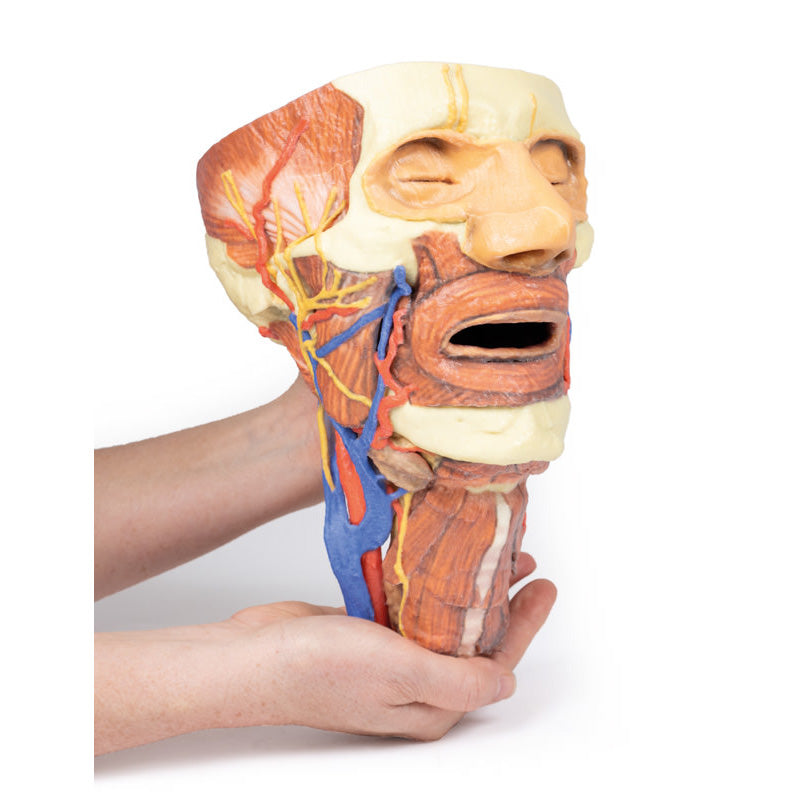

3D Printed Head and Visceral Column of the Neck

The face: On the right side of the head the parotid gland has been removed to reveal the facial nerve and all its branches (temporal, zygomatic, buccal, marginal mandibular and cervical) and demonstrate the spatial relations of structures embedded in the gland from superficial to deep (facial nerve, retromandibular vein, external carotid artery). In the surrounding region the temporalis, masseter and posterior belly of digastric are exposed, as are and the facial artery, transverse facial artery and superficial temporal artery. The facial vein and transverse facial vein are clearly visible uniting to form the common facial vein which is joined by the retromandibular vein to form the external jugular vein.

Viewed from the anterior aspect the face has been dissected to display some of the facial muscles around the mouth (buccinator [on the left], orbicularis oris and zygomaticus major). On the left side of the infratemporal fossa has been open to expose the medial and lateral pterygoids.

The lateral pterygoid is divided to show the mandibular division of the trigeminal nerve dividing into the lingual nerve and the inferior alveolar branch. Also on the left side the branches of the ophthalmic division of the trigeminal that supply the skin above the eyebrows and scalp (supraorbital [left only] and supratrochlear nerves [both sides]) are dissected. The submandibular gland is clearly visible below the mandible on both sides as are the facial arteries and veins as they course over the mandible.

The neck: The musculoskeletal portion of the neck have been removed to display the pharynx posteriorly, the larynx anteriorly, and the neurovascular bundles laterally. The suprahyoid and infrahyoid muscles can be seen on the neck, as well as the cricothyroid muscle.

When looking up the length of the trachea from below, the vocal folds are visible. The hypoglossal nerve can be seen winding around the lateral surface of the external carotid artery and the external branch of superior laryngeal nerve is seen descending in the neck. The internal jugular vein, the common carotid artery and its bifurcation into external and internal carotid arteries are clearly seen on both left and right. The vagus nerve in the carotid sheath is also visible. The ansa cervicalis is visible emerging below the digastric muscle and descending on the surface of the internal jugular vein. The internal branch of the superior laryngeal nerve can be seen below the superior thyroid artery on the left. The superior thyroid artery branching from the external carotid artery is seen descending in the anterior neck. The internal branch of the superior laryngeal artery is visible on the left piercing the thyrohyoid membrane above the inferior constrictor where this muscle is attached to the hyoid bone.

This 3D print specimen preserves a series of features of the head and visceral column of the neck:The face: On the right side of the head the parotid gland has been removed to reveal the facial nerve and all its branches (temporal, zygomatic, buccal, marginal mandibular and cervical) and demonstrate the spatial relations of structures embedded in the gland from superficial to deep (facial nerve, retromandibular vein, external carotid artery). In the surrounding region the temporalis, masseter and posterior belly of digastric are exposed, as are and the facial artery, transverse facial artery and superficial temporal artery. The facial vein and transverse facial vein are clearly visible uniting to form the common facial vein which is joined by the retromandibular vein to form the external jugular vein.

Viewed from the anterior aspect the face has been dissected to display some of the facial muscles around the mouth (buccinator [on the left], orbicularis oris and zygomaticus major). On the left side of the infratemporal fossa has been open to expose the medial and lateral pterygoids.

The lateral pterygoid is divided to show the mandibular division of the trigeminal nerve dividing into the lingual nerve and the inferior alveolar branch. Also on the left side the branches of the ophthalmic division of the trigeminal that supply the skin above the eyebrows and scalp (supraorbital [left only] and supratrochlear nerves [both sides]) are dissected. The submandibular gland is clearly visible below the mandible on both sides as are the facial arteries and veins as they course over the mandible.

The neck: The musculoskeletal portion of the neck have been removed to display the pharynx posteriorly, the larynx anteriorly, and the neurovascular bundles laterally. The suprahyoid and infrahyoid muscles can be seen on the neck, as well as the cricothyroid muscle.

When looking up the length of the trachea from below, the vocal folds are visible. The hypoglossal nerve can be seen winding around the lateral surface of the external carotid artery and the external branch of superior laryngeal nerve is seen descending in the neck. The internal jugular vein, the common carotid artery and its bifurcation into external and internal carotid arteries are clearly seen on both left and right. The vagus nerve in the carotid sheath is also visible. The ansa cervicalis is visible emerging below the digastric muscle and descending on the surface of the internal jugular vein. The internal branch of the superior laryngeal nerve can be seen below the superior thyroid artery on the left. The superior thyroid artery branching from the external carotid artery is seen descending in the anterior neck. The internal branch of the superior laryngeal artery is visible on the left piercing the thyrohyoid membrane above the inferior constrictor where this muscle is attached to the hyoid bone.